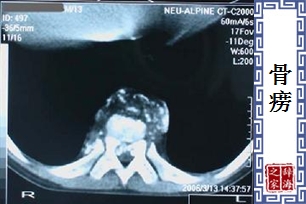

- 骨结核的别名。参见「骨结核」条。

【骨痨】 图片鉴赏